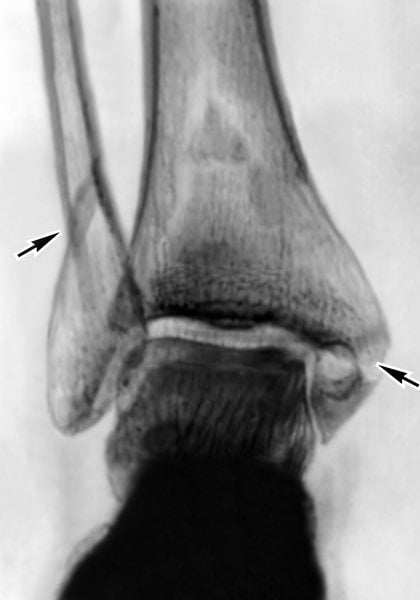

Диагностика

При подозрении на артрит проводят следующие диагностические мероприятия:

- Рентгенографию пораженного сочленения.